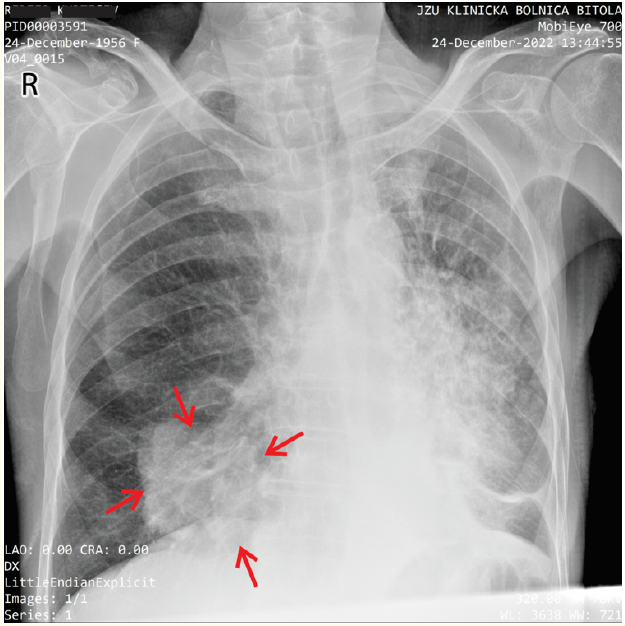

Chest X-Ray Delayed Diagnosis of Lung Cancer with Liver Metastases: Case Report of Misinterpreted Bronchopneumonia

Petar Avramovski, Marija Georgievska, Stefan Talev, Maja Avramovska, Vesna Siklovska, Biljana Ilkovska, Julijana Petrovska and Dejan Zdraveski. 6(2): 01-07.